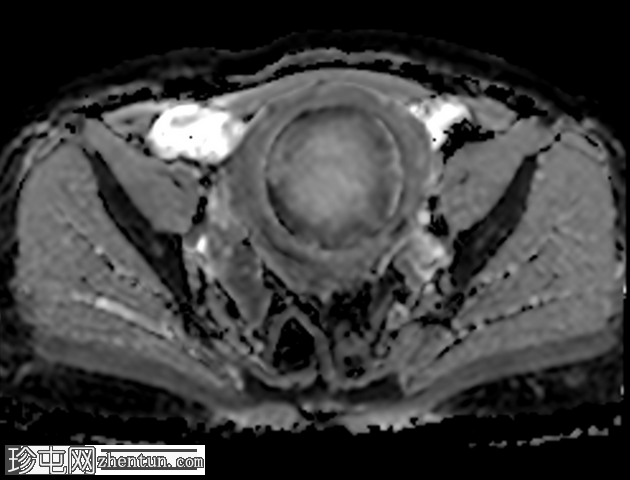

轴位

T2加权像

子宫前壁可见一边界清晰的壁内病灶,大小约7.8 × 7 × 6.8 cm。脂肪抑制T1加权像呈弥漫性高信号,T2加权像呈高信号伴低信号环,无扩散受限及对比增强。

此外,可见一个2厘米的带蒂浆膜下肌瘤,以及较小的肌壁内和浆膜下肌瘤;所有肌瘤均呈均匀强化。

盆腔内可见少量游离液体,可能为生理性。

未发现明显淋巴结肿大。

红色(出血性)变性是一种出血性梗死,由子宫肌瘤周围静脉回流受阻(静脉血栓形成)或瘤内动脉破裂引起。它最常与妊娠期间肌瘤快速生长或服用口服避孕药有关。

MRI可对子宫肌瘤进行准确诊断和定性,包括识别出血性(红色)变性等罕见并发症,并有助于将其与其他可能需要手术治疗的疾病区分开来。